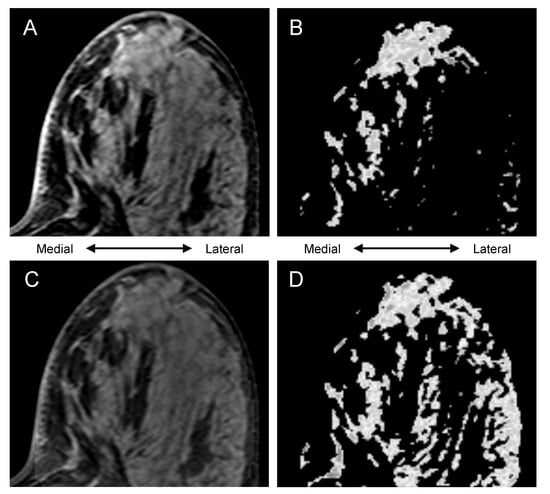

3.3. Visually Evaluated Effect of Bias Correction